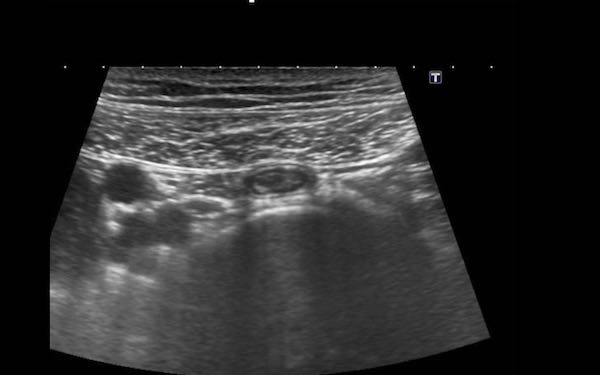

Ruột thừa bình thường (đầu mũi tên) được phân biệt với ruột non dựa vào vị trí, kích thước, sự vắng mặt của nhu động ruột, sự gắn kết với cực manh tràng (c.p.) và đầu tận cùng bịt kín (mũi tên).

Đầu mù của ruột thừa bình thường được thể hiện rõ ràng bằng cách sử dụng “kẹp mini”.